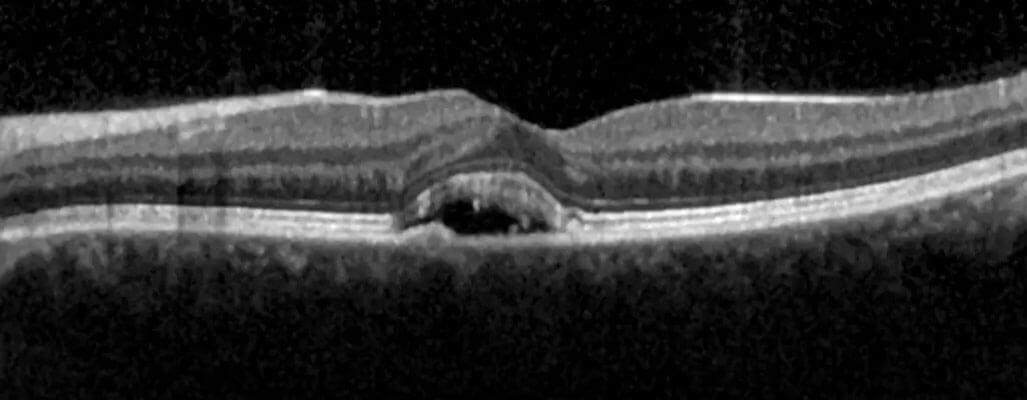

Following an examination with eye drops, CSR disease is identified using OCT (Optical coherence tomography or eye tomography). Both fluorescein angiography (FFA) and indocyanine green angiography (ICGA, ICG) are required to identify the leaky vessels in the choroid and the leak point in the retina, respectively.